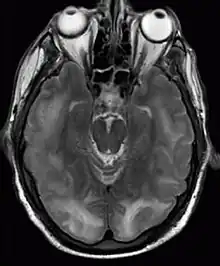

| Posterior reversible encephalopathy syndrome visible on magnetic resonance imaging as multiple cortico-subcortical areas of T2-weighted hyperintense (white) signal involving the occipital and parietal lobes bilaterally and pons. | |

The diagnosis is typically made with magnetic resonance imaging of the brain. The findings most characteristic for PRES are symmetrical hyperintensities on T2-weighed imaging in the parietal and occipital lobes; this pattern is present in more than half of all cases.[1][3] FLAIR sequences can be better at showing these abnormalities.[4] Some specific other rare patterns have been described: the superior frontal sulcus (SFS) watershed pattern, a watershed pattern involving the entire hemisphere (holohemispheric), and a central pattern with vasogenic oedema in the deep white matter, basal ganglia, thalami, brainstem and pons.[1][3] These distinct patterns do not generally correlate with the nature of the symptoms or their severity, although severe edema may suggest a poorer prognosis.[1] If the appearances are not typical, other causes for the symptoms and the imaging abnormalities need to considered before PRES can be diagnosed conclusively.[4] In many cases there is evidence of constriction of the blood vessels (if angiography is performed), suggesting a possible overlap with reversible cerebral vasoconstriction syndrome (RCVS). Diffusion MRI may be used to identify areas of cytotoxic edema caused by poor blood flow (ischemia) but it is not clear if this prognostically relevant.[1][4] Abnormal apparent diffusion coefficient is seen in about 20% of cases.[4]